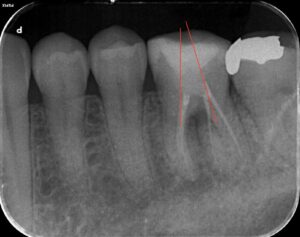

今回のケースも最小限の入り口から根管治療を行うのですが、Radix Entomolarisと呼ばれる歯根のところが難しいと予想しました。事前にCBCTを撮影して、シミュレーションを毎回行っています。あとは私が開発した方法を利用して入り口の大きさを決定しています。それが下のレントゲン写真です。

1回目の処置が先週終わり、本日2回目の治療として、ダイレクトボンディング法にて修復処置を終えました。